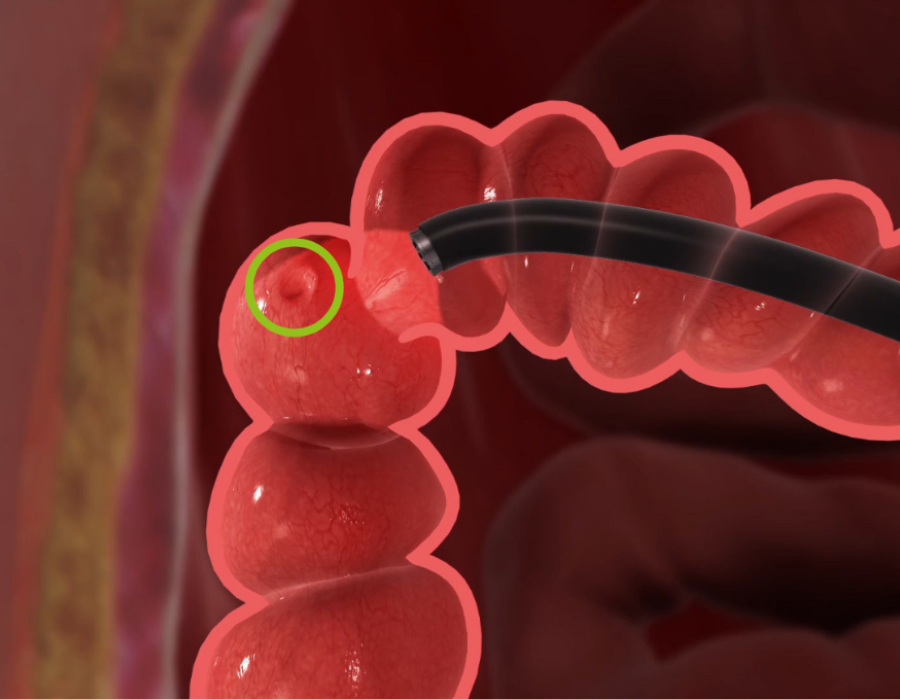

The colonoscopy procedure is nothing to feel embarrassed about. It is a simple and safe procedure where your doctor will use an endoscope – a flexible tube with a camera – called a “colonoscope” to examine your colon and rectum, looking for abnormalities called polyps. If any abnormal or precancerous polyps are present, your doctor may remove them or take a biopsy through the scope.

During the procedure, the colonoscope is inserted through the rectum and into the colon. The colonoscope is about the diameter of a pinkie finger and is lubricated to allow for easier insertion. If your doctor finds any abnormal areas during the colonoscopy, they may take a biopsy. If there any polyps are found, they may be removed and biopsied as well.

ENDOCUFF VISION is a single-use device placed on the tip of a colonoscope with soft, flexible arms that flatten the colon’s folds to bring difficult-to-see areas behind the folds into view, where polyps are often hidden and missed.